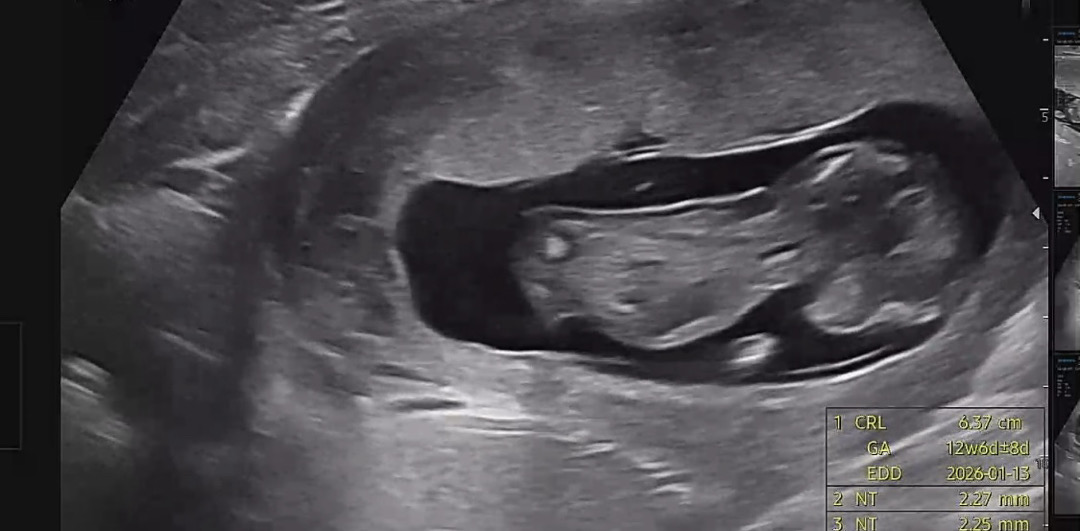

각도법 성별 궁금해요 12주 1일차

엎드려있어서 잘안보일거같긴한데,,, ㅠㅠ